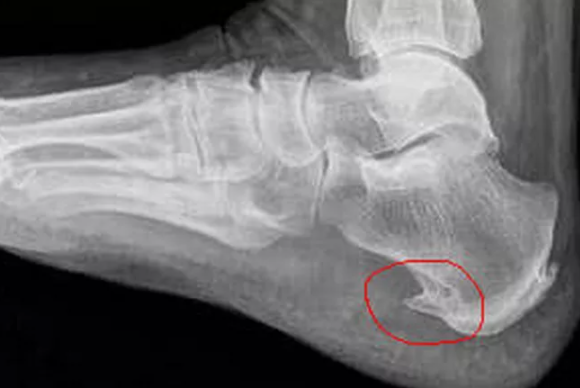

Немного о пяточной шпоре. Вкратце. Как видим на рисунках ниже, его правильное формирование зависит от состояния связок. Связки крепятся не к кости, а к надкостнице (периост).

Если связка по тем или иным причинам теряет эластичность, стянута, это может привести к отслоению (оттягиванию) участка надкостницы (периоста). Которая крепится с помощью коллагеновых пучков. В образовавшейся полости возникают воспаления, может возникать периостит (воспаление тканей надкостницы), но не об это речь.

В нашем случае, в области пяточной кости формируется кальцифицированный вырост – остеофит. При плоскостопии особенно часто натянутость связки провоцирует образование "пяточной шпоры".